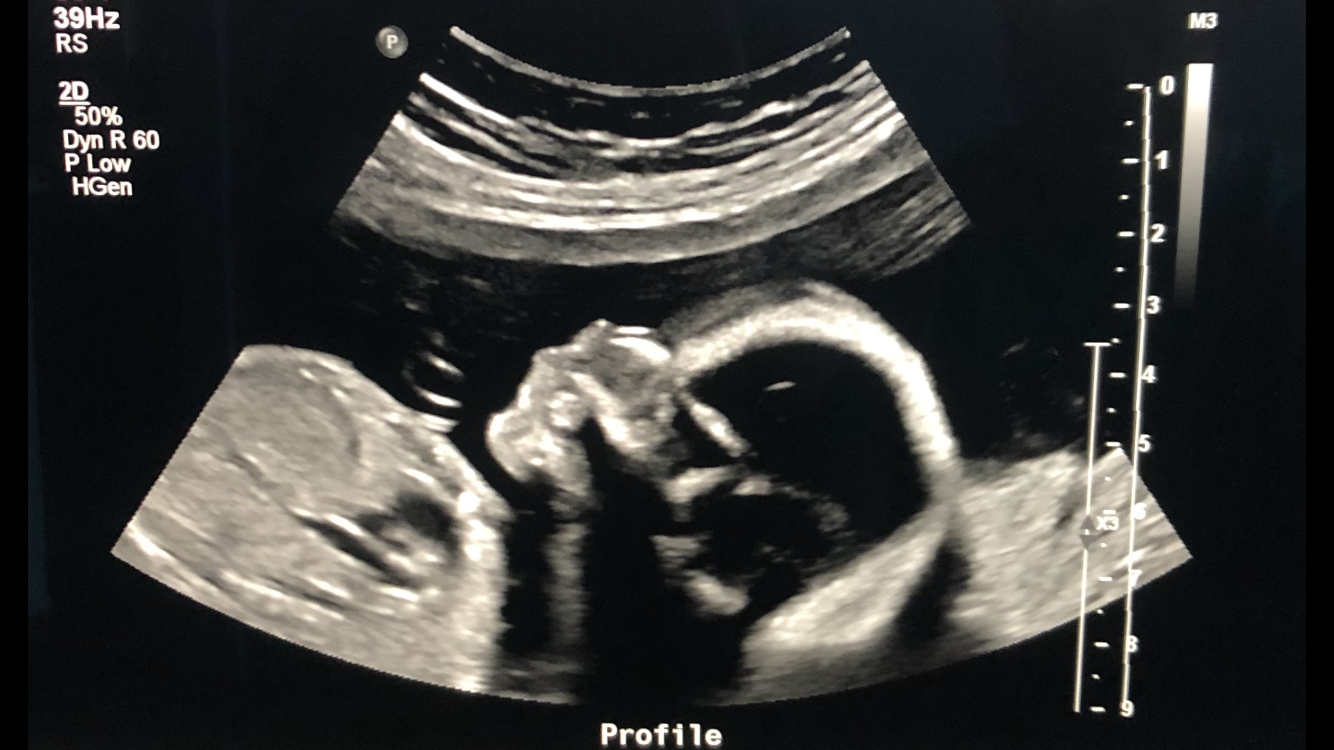

Got my NT scan done Monday and everything looked good (waiting on results of the blood work but I'm sure that looks good too!) Baby was measuring a week ahead from what I could tell and heartrate was 141. They're going to make me do my anatomy scan at the hospital. They had issues doing it in the office with my last pregnancy (tried twice then sent me over to the hospital for a 3rd try). Yay for being plus size I guess.

Baby doing great at 13w 6d last night. Unfortunately I don't know how I'm doing (short cervix) as the friendly technician clammed right up and looked grim/barely talked once she had the cervix measurements. She didn't send me to the hospital but said she only would have for an open cervix. We are still waiting for the report to arrive at my midwifery so not sure if I'll be needing a cerclage yet.

I got to see Levi today! 17w4d - they were just checking my cervical length since I had a LEEP 8 years ago. It’s nice and long at 4.5 cm! I get my anatomy scan 4/30!

So excited for this update! Baby is doing great at 16 w and my MFM doctor is amazing. My cervix measured at 2.4 cm so I may have a dynamic cervix and/or the progesterone is working. Things seems stable for now and when she pushed on my cervix it was strong so she isn't concerned about me needing a cerclage (she explained cerclage is for weak cervix). I'll be monitored biweekly till 24 weeks and then probably monthly after that. I thought I saw boy parts before I looked away but she assured me it was the cord and said she hadn't yet seen what sex the baby is. So, still team green I think!